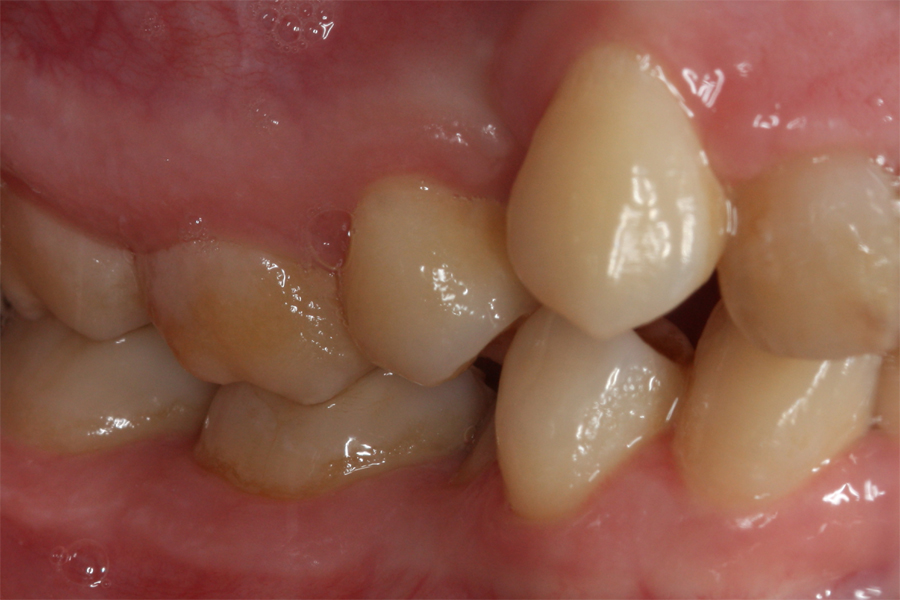

Kompleksowe leczenie zachowawczo-ortodontyczne

Młoda pacjentka zgłosiła się do naszego gabinetu celem wykonania kompleksowego leczenia zachowawczo-ortodontycznego. Oprócz problemów natury ortodontycznej stwierdzono złą higienę jamy ustnej oraz liczne potrzeby leczenia zachowawczo-endodontycznego. Po wnikliwej analizie telerentgenowskiej oraz analizie modeli zadecydowano o ekstrakcji 2 zębów w łuku dolnym (kła po stronie lewej oraz pierwszego przedtrzonowca po stronie prawej). Plan leczenia obejmował ponadto zamknięcie łuku po brakujących zębach w łuku górnym. Leczenie aktywne trwało 2 lata i 8 miesięcy. W czasie jego trwania pacjentka była regularnie poddawana zabiegom higieny profesjonalnej celem eliminacji zapaleń przyzębia brzeżnego. Po leczeniu aktywnym zastosowano leczenie retencyjne w postaci retainera stałego w żuchwie oraz szyny retencyjnej w łuku górnym.